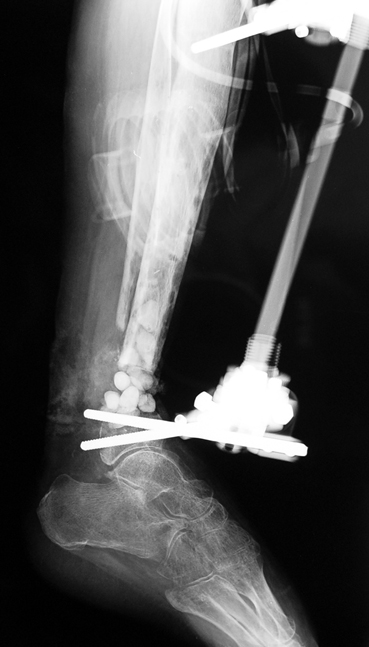

Recently, ilizarov techniques which is basis depend on distraction osteogenesis , bone segment transport or acute shortening after the resection at the site of pseudarthrosis combined with lengthening at another level of bone have been used. These treatment techniques may include some advantage for problems of infection, leg-length discrepancy, soft-tissue loss, and joint contracture.

Case 3